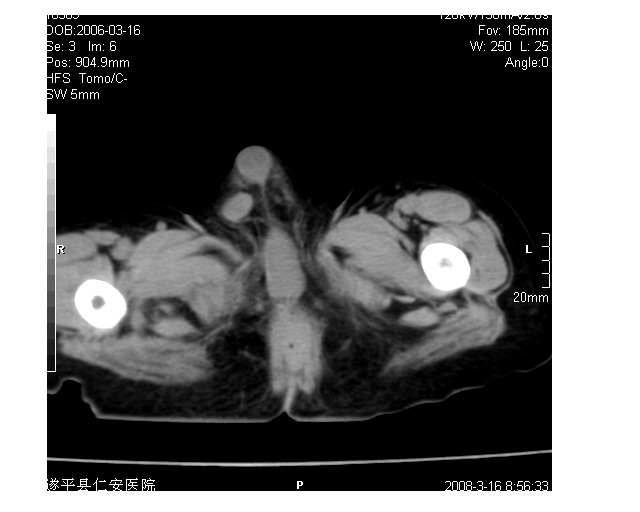

以下是引用lkc8963在2008-3-16 12:49:00的发言:[br]盆底巨大混杂密度肿块,富含多种组织成分包括脂肪/液体/软组织/钙化,边界清楚,向前压迫肠管及膀胱,向后突入骶尾部皮下脂肪层,首先考虑畸胎瘤,诊断时需要与脊柱裂/囊性淋巴管瘤等区别。